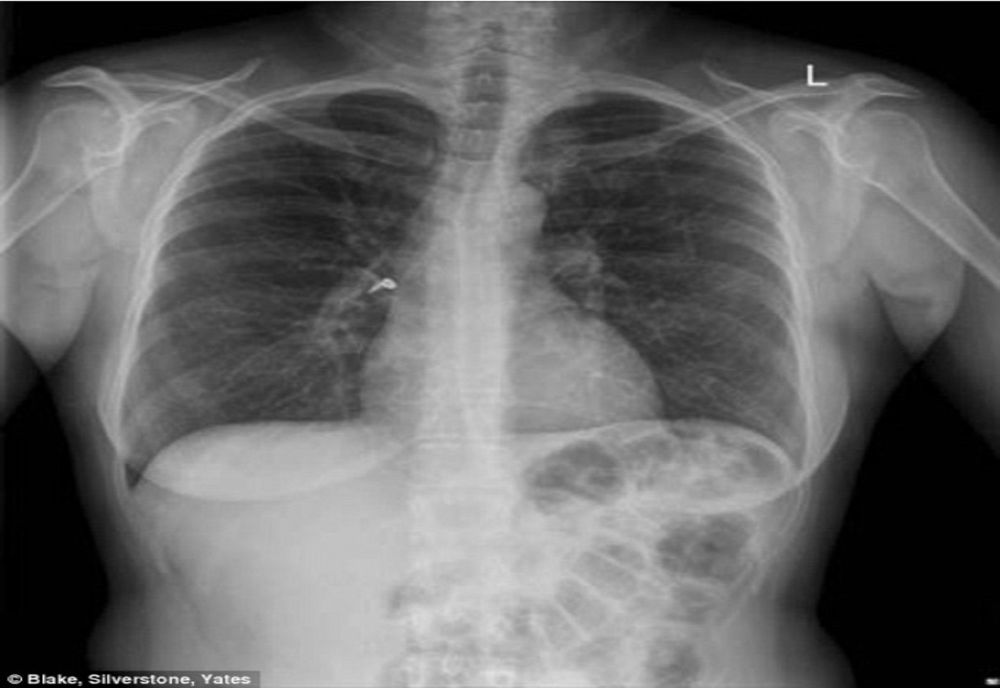

Echipamentele in valoare de 624.500 de lei vor consta într-un sistem complet de depistarea a noului coronavirus, două izolete, trei tuneluri dezinfectante şi un sistem prin care radiografiile vor putea fi examinate în format digital,